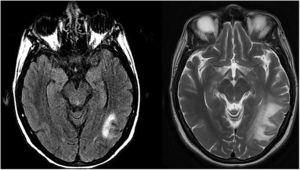

Mujer de 45 años con antecedentes de depresión y múltiples visitas a Urgencias, hospitalizada con el diagnóstico de brote psicótico. Presentaba una actitud oposicionista, delirios de persecución, alucinaciones auditivas y agitación. No mejoró con fá rmacos antipsicóticos. La exploración neurológica fue normal. Se detectó linfopenia (600/mm3) y el test del VIH resultó positivo (carga viral superior a 1.000.000 copias/mL y recuento de linfocitos CD4+ 60 células/mm3). La IRM cerebral mostró una lesión hipointensa-T1 e hiperintensa-T2, localizada en sustancia blanca temporo-occipital izquierda y parietal derecha, sin restricción a la difusión y sin efecto masa (fig. 1a). Se detectó ADN del virus JC en líquido cefalorraquídeo (LCR) y se descartaron otras infecciones. Se diagnosticó LMP.

Se inició TAR (tenofovir-alafenamida, emtricitabina y bictegravir) y la sintomatología psiquiá trica remitió. Fue dada de alta asintomá tica. Un mes después, los linfocitos CD4+ eran 274/mm3 y la carga viral era indetectable. Dos meses tras iniciar la TAR, refería pérdida progresiva de visión. La IRM objetivó un aumento de las lesiones con efecto expansivo (fig. 1b), se descartó patología ocular y, con el diagnóstico de probable SIRI, se inició tratamiento con dexametasona (4 mg/12 h) durante tres semanas; posteriormente, se redujo la dosis hasta suspender en cuatro semanas. Cuatro meses tras iniciar la TAR, la paciente ingresó por convulsiones y ceguera incapacitante. Con pruebas de imagen y estudio de LCR, se descartaron otras causas, se asumió SIRI y se reinició dexametasona (4 mg/8 h). Se controlaron las convulsiones, pero persistió el déficit visual (OD -10,5 y OI -9,5). La paciente fue ingresada en un centro sociosanitario.